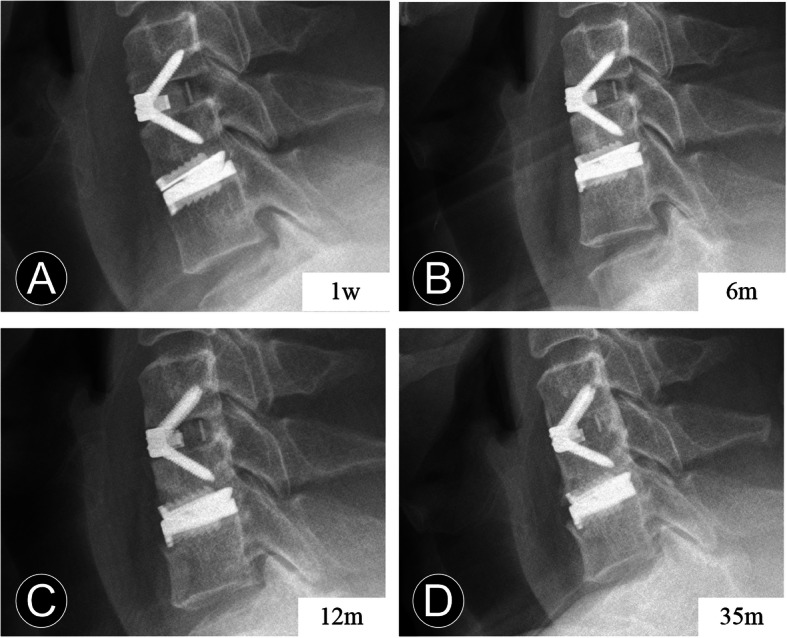

Fig. 3.

Serial postoperative radiographs of a 40-year-old man who underwent contiguous 2-level hybrid surgery at C5-C7. a and b The immediate and 6-month postoperative lateral radiographs show the peri-prosthesis bone loss and anterior heterotopic ossification. c At the last follow-up, the lateral radiograph shows the anterior heterotopic ossification developed

Fig. 4.

Serial postoperative radiographs of a 47-year-old man who underwent contiguous 2-level hybrid surgery at C5-C7. a and b The lateral radiographs show the anterior bone loss occurred at 6 months after surgery. c and d The 12-month and 35-month postoperative lateral radiographs show the anterior heterotopic ossification occurred after the non-progressive bone loss

However, excessive bone loss may lead to prosthesis subsidence [21] (Fig. 1), and severe HO could obviously affect the motion-maintaining function of CDA (Fig. 3), contrary to its design philosophy. Therefore, the balance of the bone reconstruction process are essential to avoid complications after CDA and HS. The study also suffers from some other limitations. First, the retrospective nature of our study may be associated with bias, especially in radiographical measurements. Second, different prostheses with distinct biomechanical characteristics may be diverse in bone reconstruction. Third, comparisons of characteristics among the different ABL-degree groups need further attention. A specific study design with multivariate analysis of large-scale and longer follow-up would be important.